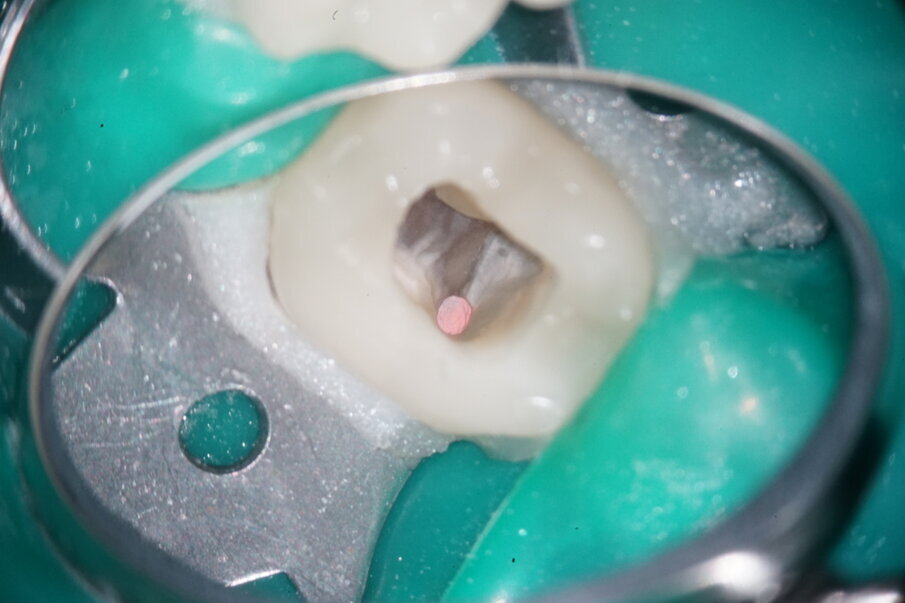

After applying the dental dam and preparing the access cavity, the next step was to remove the existing obturation material (Figs. 3 & 4). A high-speed rotary HyFlex Remover was used for this purpose (Fig. 5). The revision file efficiently removed the materials from the root canal so that additional solvent could be dispensed with during treatment. Unlike in other cases, the plastic carriers in this case were not extracted with an aid, but were machined (see video above). The non-cutting tip of the retreatment file protects the surrounding tooth structure during this procedure, which makes handling even easier.

Fig. 4: Initial situation of distal canals.